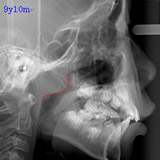

アデノイドの大きさについて

左はほぼ正常の状態で、わずかな腫れが認められますが問題ありません。

真ん中は軽度の腫れで、気道(空気の通り道)を少しふさいでいます。この場合は経過観察、または必要があれば耳鼻科で管理していただきます。

右は腫れが強く、気道をふさいでいます。この状態では鼻呼吸が困難であり、歯列、顔面発育にも影響がでる可能性が大きくなります。耳鼻科での治療を強くお勧めます。